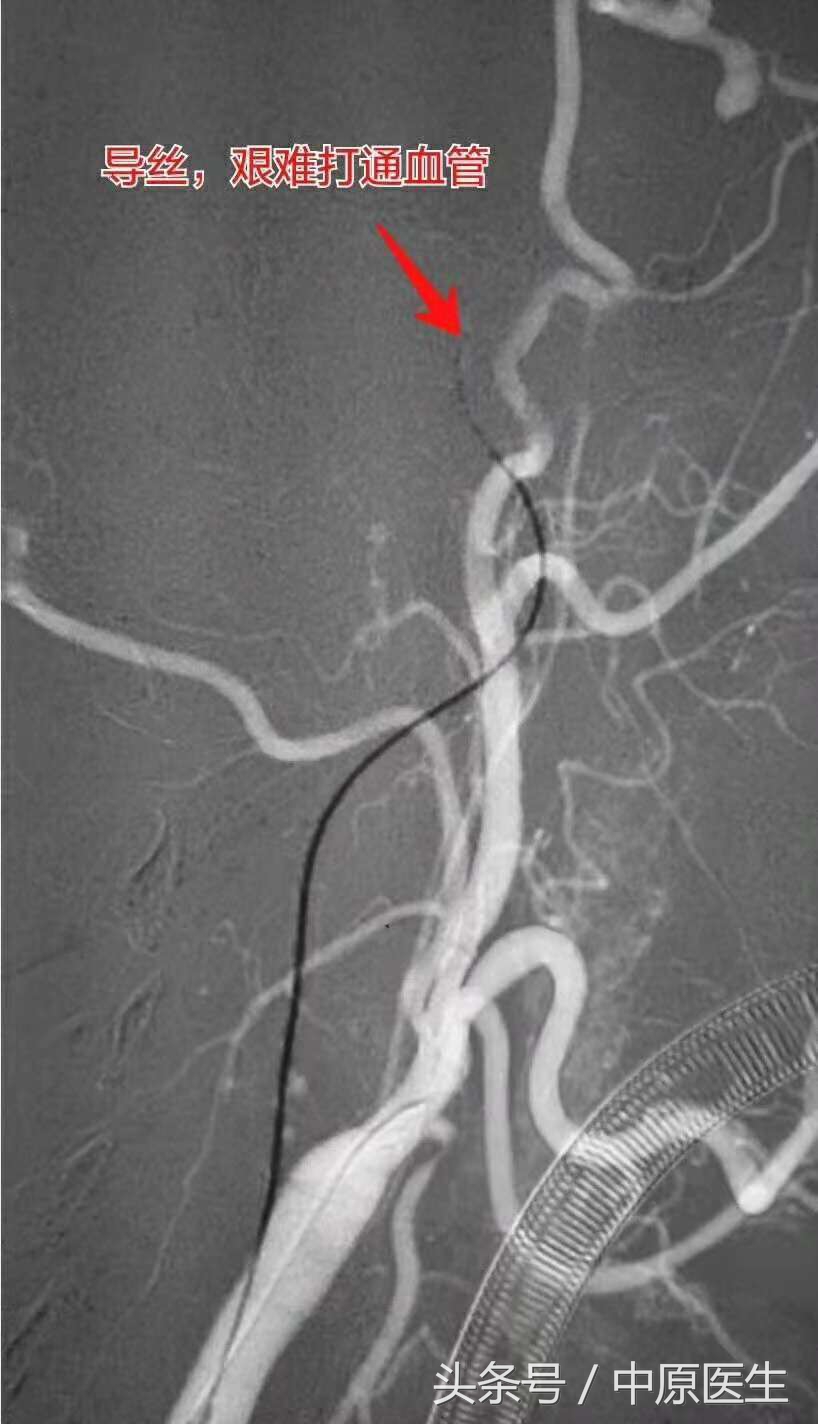

脑血管造影发现,患者的右侧颈内动脉全程闭塞了,而且,一点残端都没剩下,这种情况,通常是血管闭塞很久了,决不止一个月。

没有血管残端,若想打通血管,导丝没有着力点;闭塞的时间太久,陈旧血栓早已纤维化,一根塑料绳似的,无法打通。

感谢病人家属的信任(不论成败,强烈要求我们手术尝试),通过艰苦的努力,成功打通了血管。术后血管造影吓出一身冷汗:他颅内有个动脉瘤!由于血管是闭塞的,事先不知道啊!要是盲目摸进动脉瘤腔,捅破了动脉瘤,老天爷,那才是不堪设想。